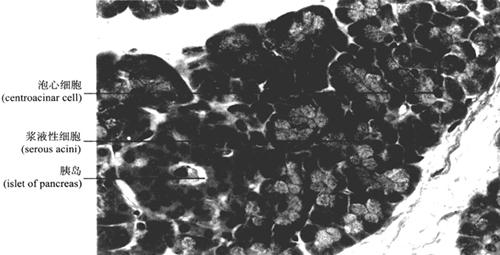

2.胰腺的组织结构胰腺(pancrease)表面有薄层结缔组织被膜。实质由外分泌部和内分泌部组成(图9-48)。

图9-48 胰腺(400×)

(1)外分泌部:占胰腺实质的大部分,为复管泡状腺,由腺泡和导管组成。腺泡属纯浆液性,由一层锥体形的腺细胞组成,细胞顶部呈嗜酸性,含大量酶原颗粒,基底部含丰富粗面内质网,故呈碱性。腺泡腔内常见扁平而染色浅的泡心细胞(centroacinar cell)(图9-48、图9-49),是伸入腺泡腔内的闰管上皮细胞。与腺泡相连的细长导管称闰管(intercalated duct),直接与小叶内导管相连,无分泌管,小叶内导管汇入小叶间导管,再汇合到胰主导管(main pancreatic duct)。导管上皮由单层扁平上皮移行为单层柱状上皮,胰主导管管壁较厚,为单层高柱状上皮,从胰尾至胰头行经胰腺全长,大部分主导管先与胆总管汇合后再通入十二指肠,故胆道疾病有可能诱发胰腺病变。外分泌部分泌含胰蛋白酶、胰脂肪酶、胰淀粉酶等多种消化酶的胰液,消化食物。

图9-49 胰腺腺泡泡心细胞模式图

(2)内分泌部:称胰岛(pancreatic island),是散在外分泌部之间的内分泌细胞团。成人胰岛约100万个,胰岛大小不等,含丰富的毛细血管。多见于胰尾部,在HE染色切片中胰岛细胞着色浅,难以分类,用Mallory-azan染色法可分为A、B、D三种细胞。